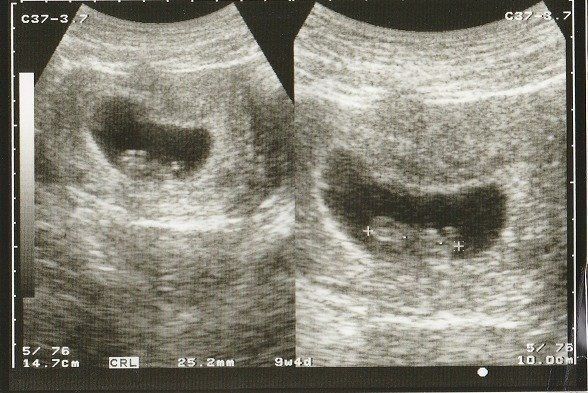

たかこさんの妊娠9週目のエコー写真 心拍を確認後、順調に大きくなってきた

胎嚢がぐっと大きくなり、頭と胴体が分かれています。左の丸い部分が頭で、右が胴体のようです。ようやく、「母子手帳をもらってきて」と言われましたが、やはりすぐには受け取りに行けませんでした。だんだんとつわりがひどくなり、空腹時は胃がムカムカし、食べると気持ち悪い状態が続きました。お腹の張りと、めまいがあったのもつらかったです。